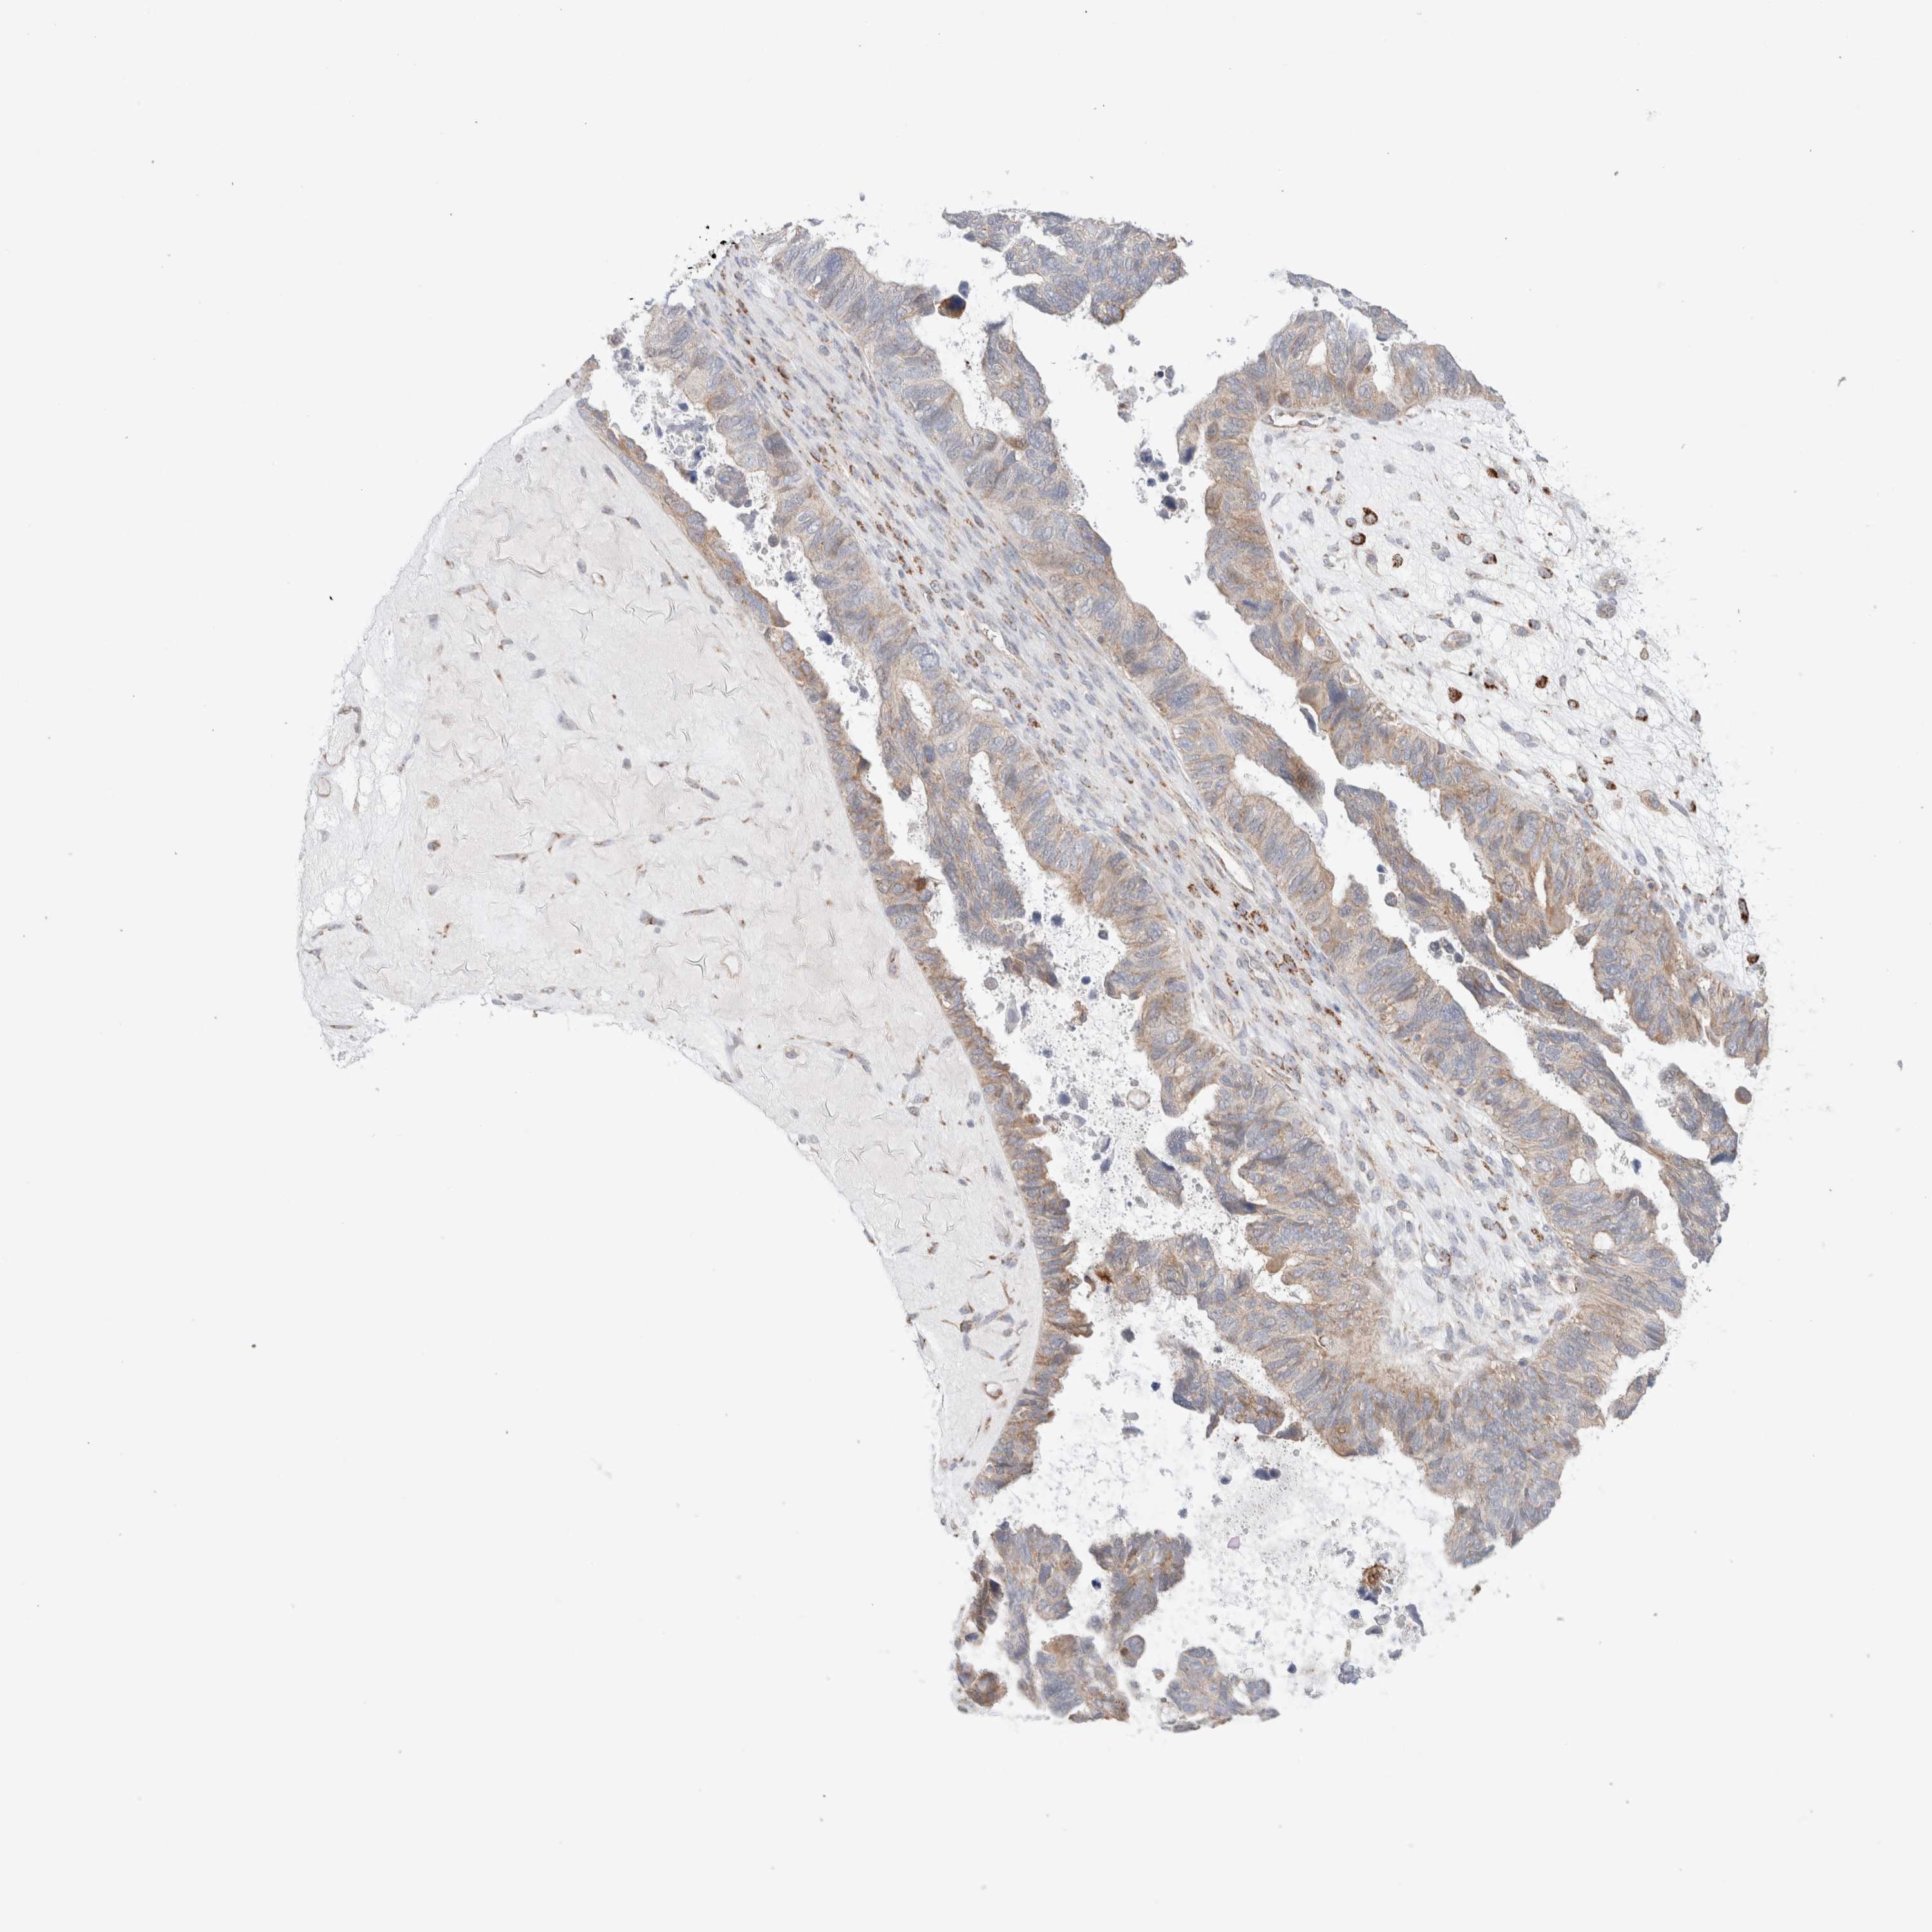

OVARIAN CANCER - Protein expressioni

A mouse-over function shows sample information and annotation data. Click on an image to view it in a full screen mode. Samples can be filtered based on level of antibody staining by selecting one or several of the following categories: high, medium, low and not detected. The assay and annotation is described here.

Note that samples used for immunohistochemistry by the Human Protein Atlas do not correspond to samples in the TCGA dataset.

Antibody stainingi

Antibody staining in the annotated cell types in the current human tissue is reported as not detected, low, medium, or high, based on conventional immunohistochemistry profiling in selected tissues. This score is based on the combination of the staining intensity and fraction of stained cells.

Each image is clickable and will lead to virtual microscopy that enables deeper exploration of all samples and also displays staining intensity scores, fraction scores and subcellular localization as well as patient and tissue information for each sample.

Antibody HPA022534

Antibody HPA023031

Antibody HPA023292

Carcinoma, endometroid

Cystadenocarcinoma, mucinous, NOS

Carcinoma, NOS